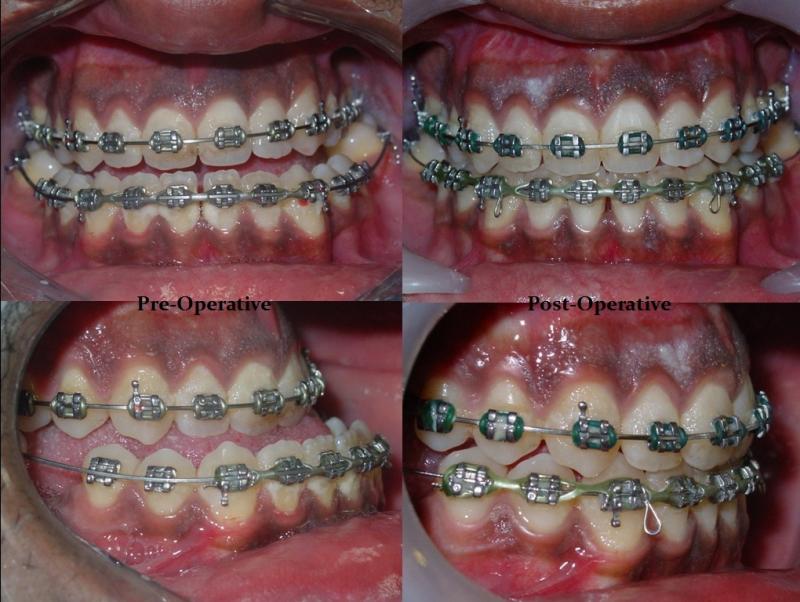

Diagnosis and treatment of dysgnathia, and orthognathic reconstructive surgery, genioplasty, maxillo-mandibular advancement/set-back, and surgical correction of facial asymmetry (See Images Below)

Orthognathic Surgery (Class II)

Orthognathic Surgery (Class III)

Orthognathic Surgery (Class II with 'Gummy Smile')